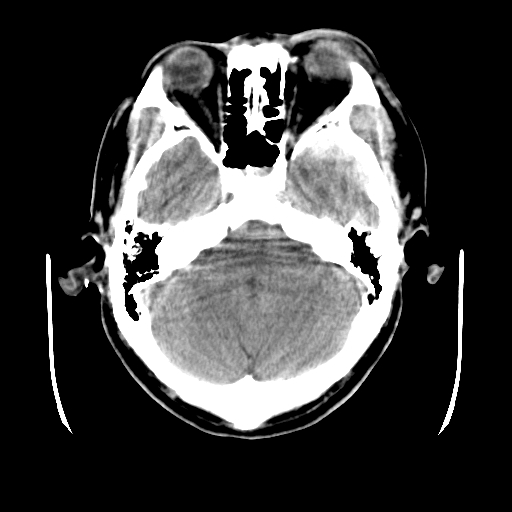

标题: CT25225:男,51岁,头外伤一小时。 [打印本页]

标题: CT25225:男,51岁,头外伤一小时。

男,51岁,头外伤一小时,呕吐两次。

左侧颞部硬膜外;蛛网膜下腔出血 ;脑肿胀

1)左侧中颅窝蝶骨翼后方硬膜外血肿。2)左侧颞顶部硬膜下血肿。3)蛛网膜下腔出血。4)左侧筛窦及双侧蝶窦炎症(或积血)。5)左侧额部头皮软组织肿胀。

左侧硬膜外 下血肿  硬膜下血肿影不出外是蛛网膜下腔出血

左颞顶不头皮血肿,左侧颞不硬膜(下)血肿,蛛网膜下腔出血

1:左侧硬膜外及硬膜下混合血肿。2:蛛网膜下腔出血。3:左额部少量颅内积气?

左颞部硬膜外血肿,蛛网膜下腔出血,副鼻窦积液.头皮损伤.